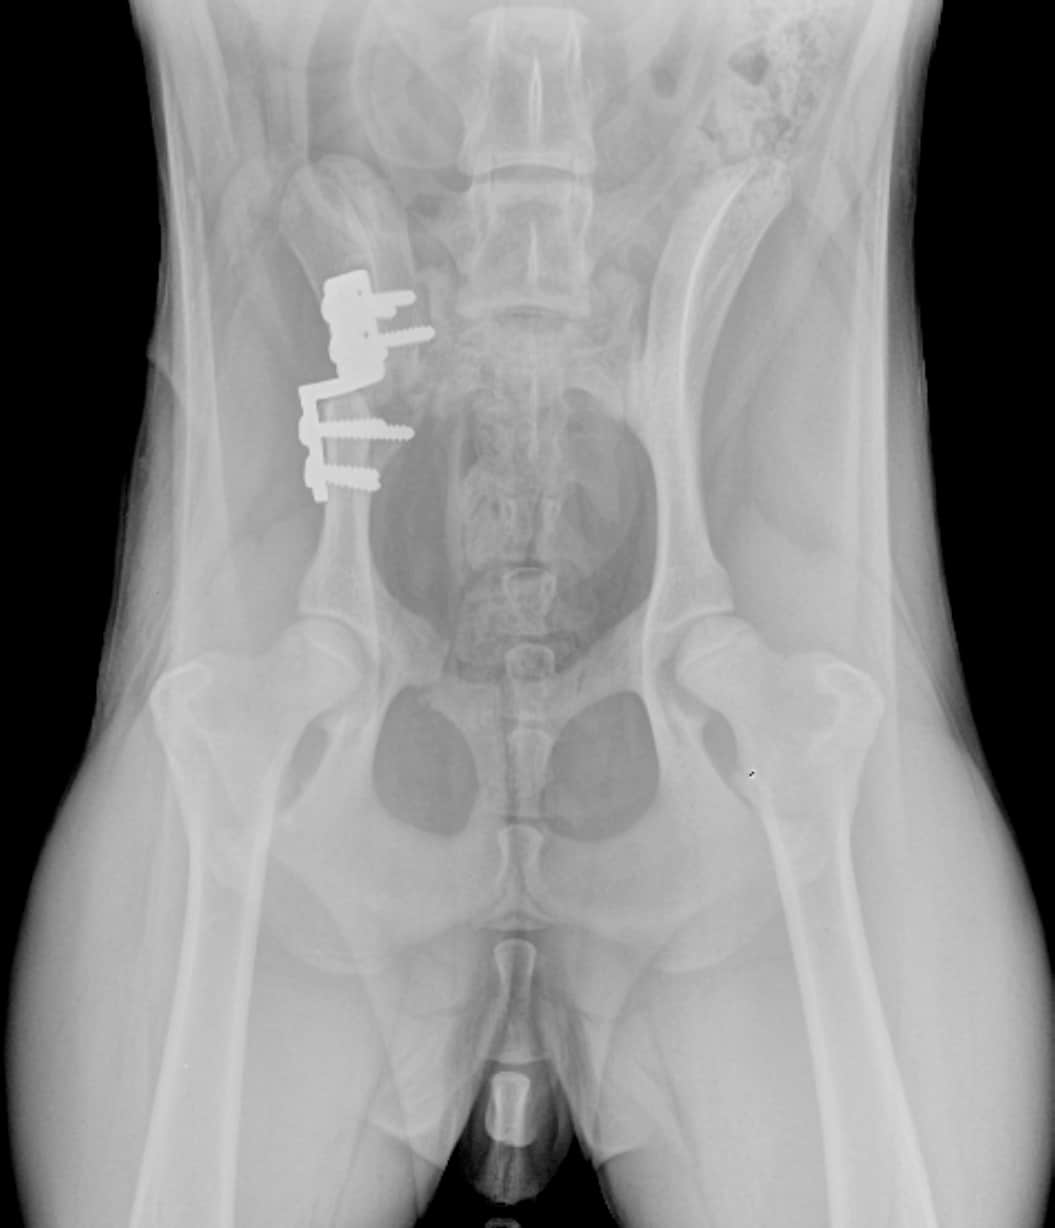

Dysplasie de la hanche chez le chien